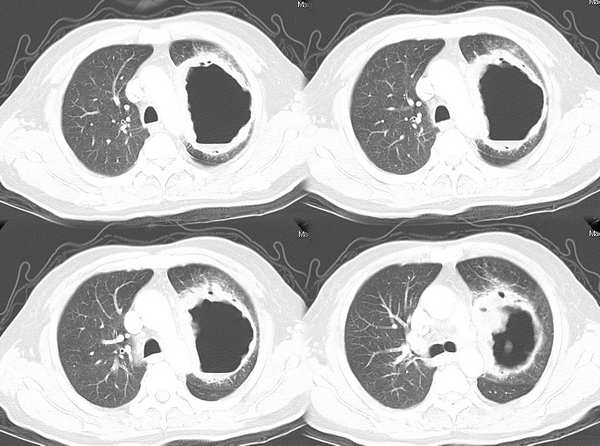

肺癌--腺癌

ct1746 pingfanjun提供 结果右上肺腺癌

76岁;咳嗽、咯血、气短、呼吸困难一年余

http://www.radida.com/radinet/read.php?tid=5255

ct1847 九目段提供

m/71y,咳嗽咳痰,痰中带血,低热。

http://www.radida.com/radinet/read.php?tid=7356

ct1962:mzjctmr提供 肺穿病理结果为腺癌

女性,43岁,刺激性干咳4个月,血象血沉正常,无发热

http://www.radida.com/radinet/read.php?tid=7602

ct2060 liuzhiguang 提供 病理中分化型腺癌

http://www.radida.com/radinet/read.php?tid=8557

ct2240 mzjctmr提供 病理结果为高分化腺癌并支气管淋巴转移

女性,60岁,夜间发热一周余就诊。体温38度,血沉35mm/h

http://www.radida.com/radinet/read.php?tid=8574

ct1154 听蝉观竹提供 结果-------肺小细胞癌

http://www.radida.com/radinet/read.php?tid=3361

ct1649:guzhongliangddd提供 胸部腺癌

http://www.radida.com/radinet/read.php?tid=4865

ct2209:guzhongliangddd提供 病理结果腺癌

男,42。体检偶然发现。纵隔肺门无增大淋巴结

http://www.radida.com/radinet/read.php?tid=8397

ct2182 丁海岸提供 穿刺,结果为肺鳞腺癌http://www.radida.com/radinet/read.php?tid=8348

ct2607 jiajie提供 手术肺叶切除,病灶大小约6x5cm,边缘有小溃口。

病例结果:未分化癌(巨细胞癌?),肺门两枚淋巴结查到癌细胞。

男性,37岁,咳嗽、胸闷,无咳血,无明显发热病史。体形消瘦。

http://www.radida.com/radinet/read.php?tid=9732